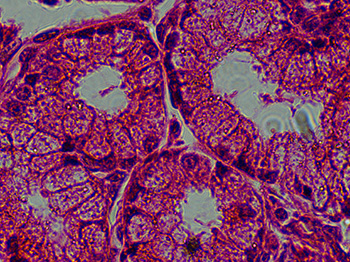

Microscope Image Comparison: ZEISS Primostar versus Motic Panthera

Recently, we looked at images on two different microscope systems: the ZEISS Primostar 3 and the Motic Panthera. We wanted to compare the images captured with both of these microscopes.

For both microscopes, the same digital camera was used to capture the images, a 5 megapixel microscope camera (the DCM5.3). Images displayed were captured with a 100x objective lens. For the ZEISS Primostar 3, the Zeiss iPlan Achromat 100x Objective was used. The Motic UC Plan Achromat 100x objective lens was used on the Motic Panthera microscope.

We found that the images taken with the ZEISS Primostar 3 and the Motic Panthera microscopes were comparable, and you can see for yourself in the table below.